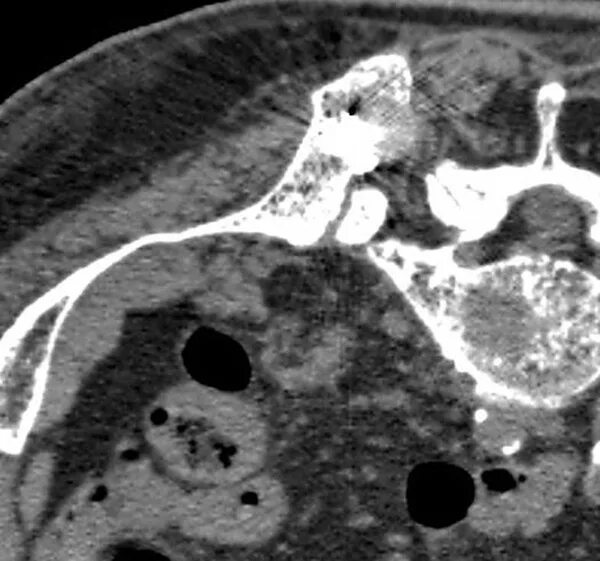

Метастазы в костном мозге